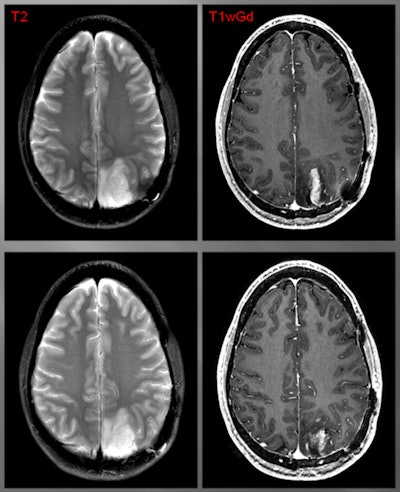

Image comparisons

The subjects were injected with 2 to 5 mCi (74 to 185 MBq) of CLR1404 and imaged with PET/CT six hours, 24 hours, and 48 hours after injection. Fourteen patients were followed until surgery or with gadolinium-enhanced MRI for six months or longer.

The researchers found avid CLR1404 uptake in 12 of the 16 patients; four individuals with cancer recurrence (as opposed to pseudoprogression) had no tracer uptake. There was no significant uptake of CLR1404 in normal areas of the brain and no uptake in regions that were treated for cancer and were presumably tumor-free.

CLR1404-PET successfully imaged tumors with high tumor-to-background uptake and uncovered larger tumor volumes than contrast-enhanced MRI.

"We saw areas of concordant and discordant PET uptake and MRI enhancement," Hall said. "This is what we are really excited about, those discordant areas. Those are the areas where we have the ability to add perhaps more accurate complementary information to what MRI shows."